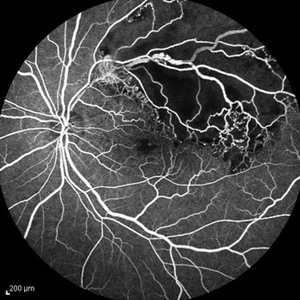

Behcet's Disease Behcet's DiseaseMar 13 2013 by Hamid Ahmadieh, MD Wide field FA of the right eye of a 23-year-old man with retinal vasculitis and branch retinal vein occlusion (BRVO) due to Behcet's disease . Photographer: Solmaz Shahmohammad, Negah Eye Center, Tehran Imaging device: Heidelberg Spectralis Condition/keywords: branch retinal vein occlusion (BRVO), retinal vasculitis

Behcet's Disease Behcet's DiseaseMar 13 2013 by Hamid Ahmadieh, MD Wide field FA of the left eye of a 23-year-old man with retinal vasculitis due to Behcet's disease . Photographer: Solmaz Shahmohammadi , Negah Eye Center, Tehran Imaging device: Heidelberg Spectralis Condition/keywords: retinal vasculitis